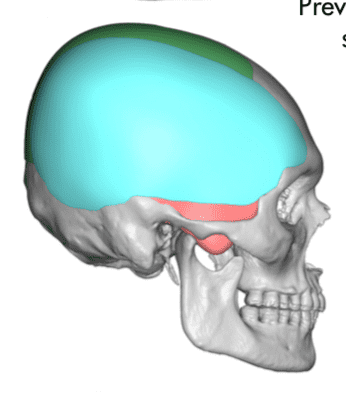

Desire for head shape asymmetry improvement as the final stage of total skull reshaping surgeries. (previous skull implants are in green color)

Placement of custom temporal implant through an incision behind the ear.

Desire for head shape asymmetry improvement as the final stage of total skull reshaping surgeries. (previous skull implants are in green color)

Placement of custom temporal implant through an incision behind the ear.